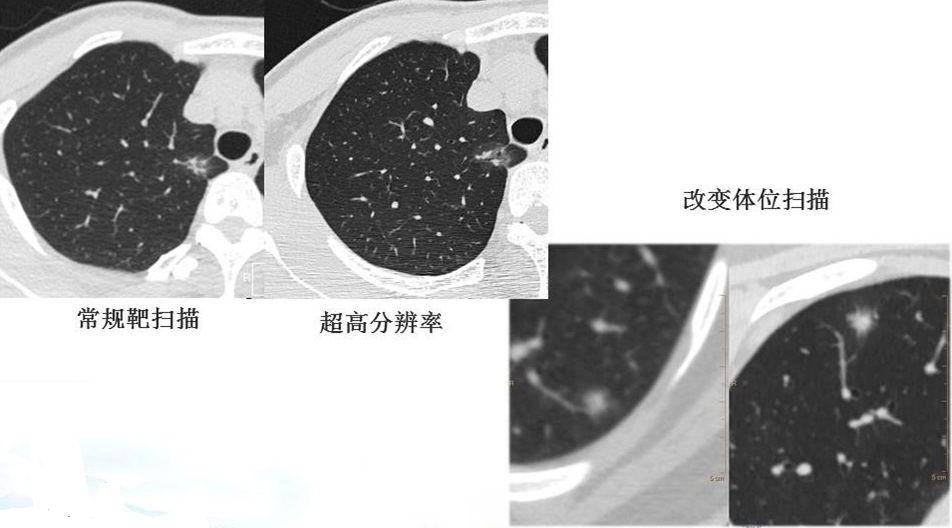

综上所述,目前最高大上的肿瘤全身PET-CT检查也不能确诊肺微/小结节的良恶性。PET-CT检查最适用于那些直径>8-10mm,且具有中度恶性肿瘤概率的实性或半实性肺结节的评估,以及对肺部结节的术前分期。对于<8mm的肺小/微结节,PET-CT检查诊断价值不高,不常规推荐行PET-CT检查。那么对于<8mm肺微小结节怎么来确诊其良恶性呢?我们可以通过肺螺旋CT薄层扫描、三位重建的结节分析,根据其结节大小、形状、密度(以貌取人,兼顾内涵),以及是否有恶性结节所具有的分叶征、毛刺征、空泡征、支气管充气征、血管征、胸膜凹陷征等来判断其良恶性,更重要的是结合动态随访观察,方能判断其结节良恶性。